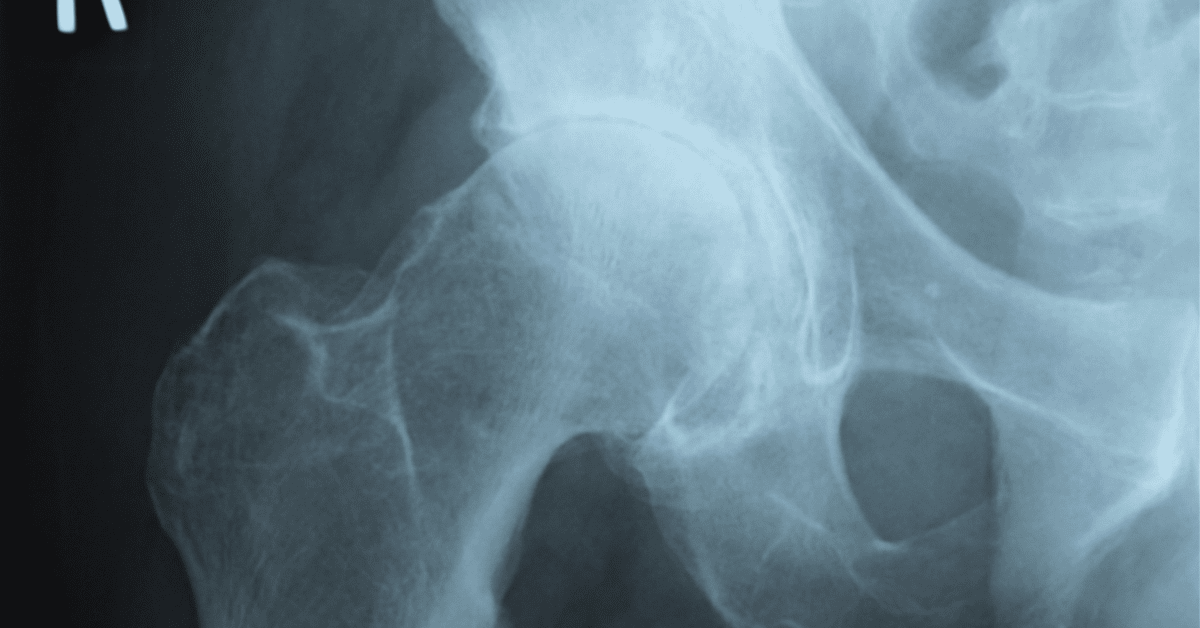

股関節の変形など構造的な問題

年齢を重ねると骨は変形します。

骨と骨でできている空間が狭くなったり、骨に棘ができたりして、通常では問題ない動きであっても、痛みが出たり違和感が出るようになります。

股関節は荷重関節と呼ばれる体重を支持する役割を持つ関節ですので、年齢とともに変形が出やすい関節です。

変形があるからといって、必ずしも痛みが出るというわけではありませんが、上記に挙げた鼠蹊部痛の特徴が全て当てはまずに画像所見で変形が明らかである場合は股関節と股関節周辺の靭帯などの組織が痛みを出している可能性が高いです。